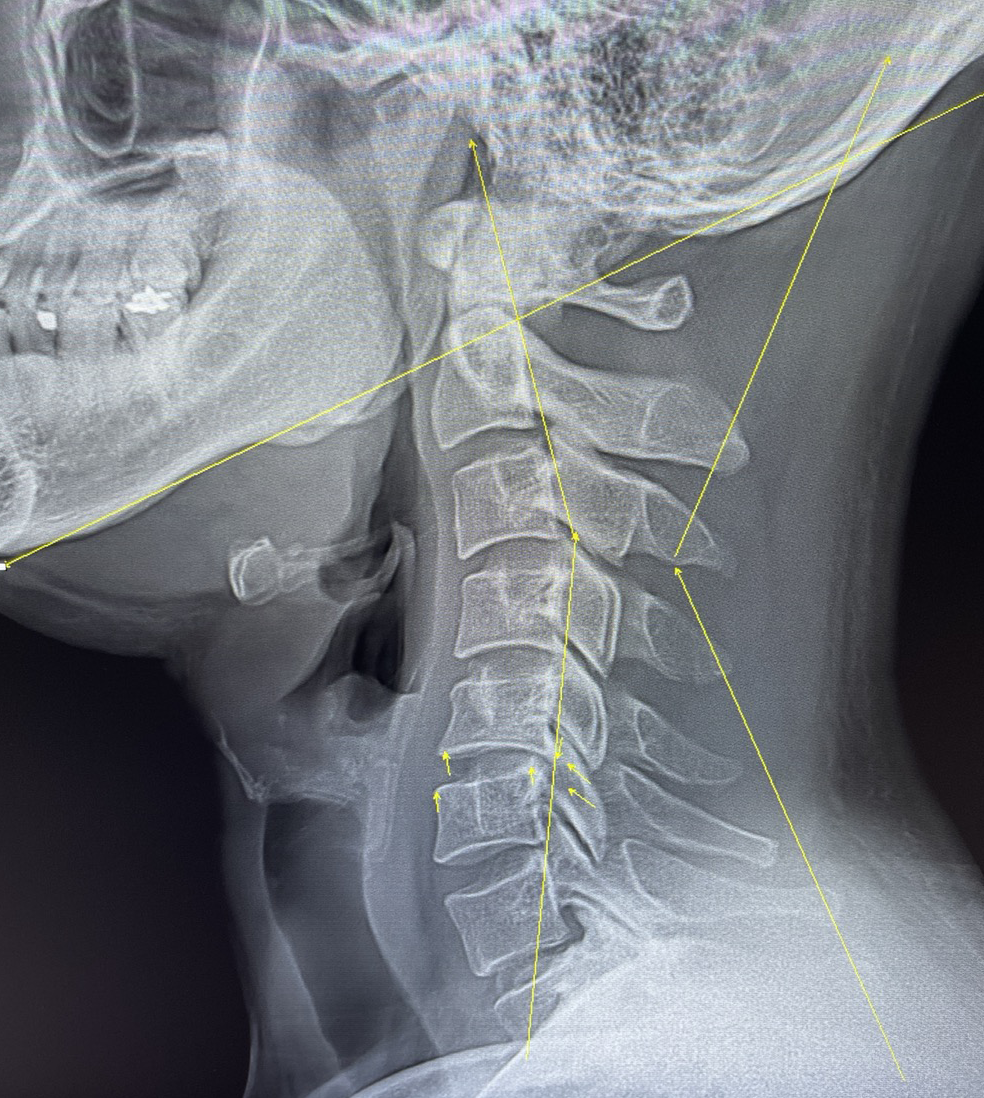

정확한 진단을 위해 경추부 X선 촬영(X-ray)이나 자기공명영상검사(MRI) 등의 정밀검사를 해야 합니다.

위의 사진은 실제 저의 목을 MRI 촬영한 사진입니다.

정말 너무 고통스럽고 아픈 완벽한 거북목입니다.

자연스러운 C자형 목이 아닌, 역 S자형 목입니다.